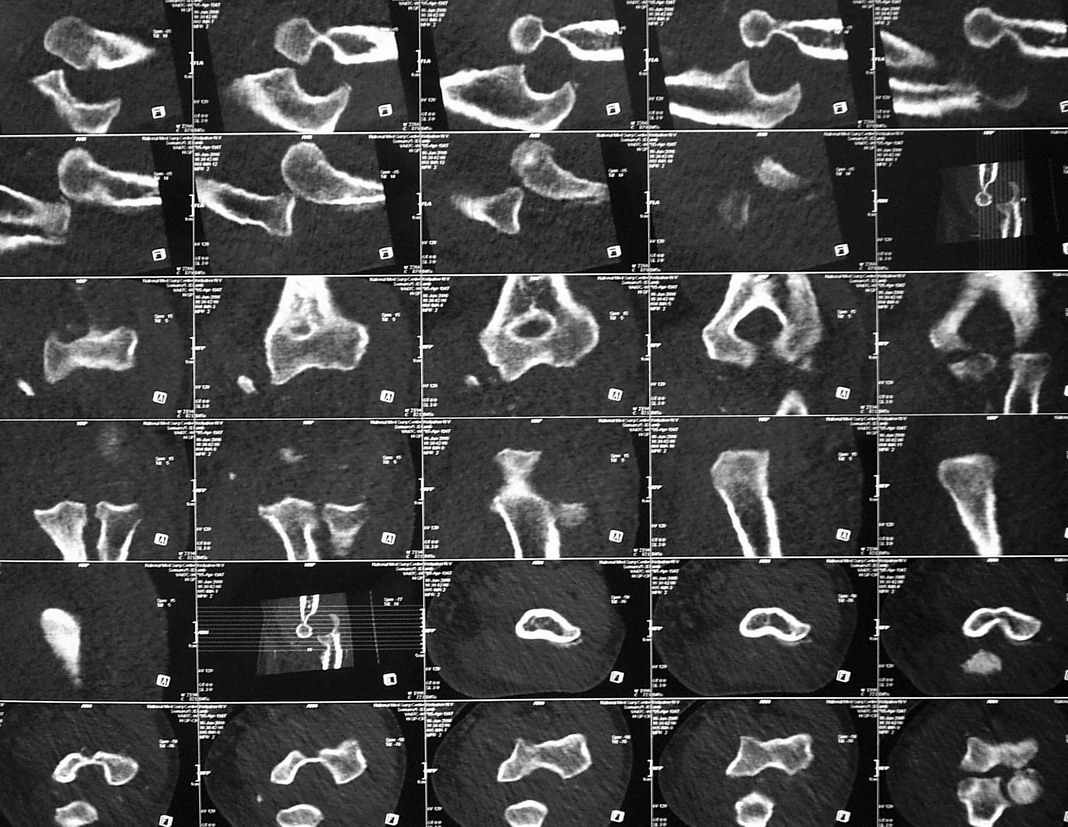

3 недели лечился в травмпункте с диагнозом отрывной перелом медиального надмыщелка левой плечевой кости (Rtg-1). Лечение состояло в ношении руки на косыночной повязке. Затем в другом учреждении сделали КТ (рис 2,3,4).

На R-граммах имеется отрывной перелом внутреннего мыщелка плечевой кости (суставной поверхности). Взаимоотношения в суставе правильные. На КТ - задний вывих предплечья. А не вправляли ли в травмпункте предплечье, не наложив затем гипсовой иммобилизации??? Чтобы предплечье вывихнулось в косынке - ... я не встречал... По тактике - оперативное лечение и чем быстрее, тел лучше. Время идет сейчас не на пользу. Идти задним доступом либо с остеотомией локтевого отростка, либо с V-образным рассечением сухожилия трицепса. Костный свободный фрагмент желательно удалить.

Удивлен такими различиями между КТ и Rtg... никогда с таким не встречался. а рентген-снимках никакого намека на вывих не вижу, поэтому и обвинять в халатности персонал травмпункта не стоит. Хотя вполне вероятно, что пальпаторно можно было заподозрить несоответствие обследования с реальной картиной.

Чудеса конечно бывают, но не настолько же? Если рентгенограммы и томограммы одной конечности, то они явно разнесены по времени и событьиям. Нужно что-то повторить Rg или КТ и тогда уже думать. С уважением Шевырев К.В., МОНИКИ